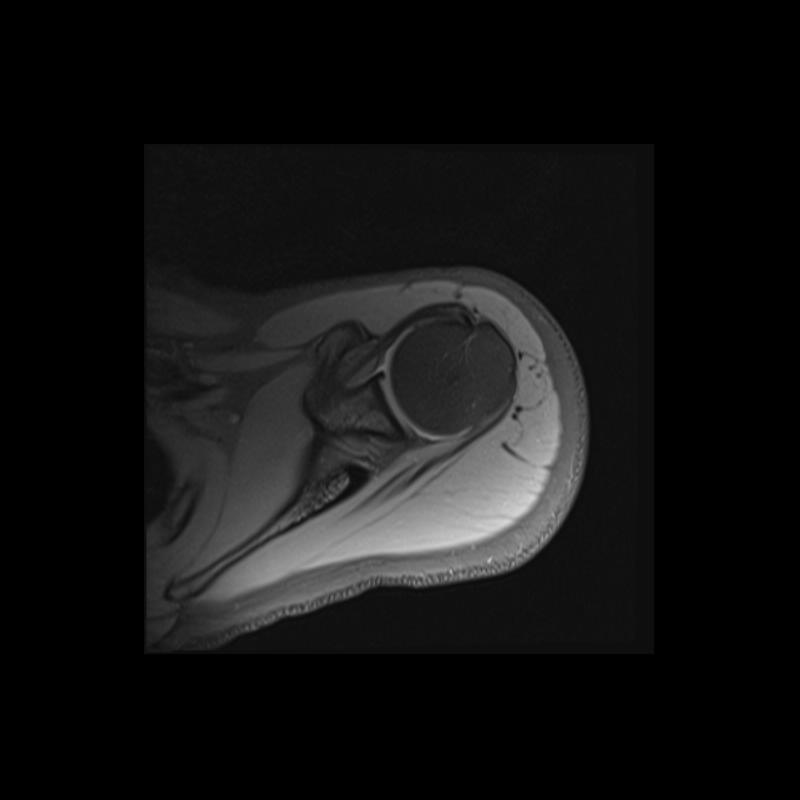

Shoulder MRI Anatomy